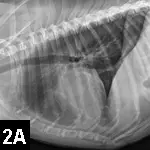

Imaging & Laboratory ResultsA peripheral catheter was placed and shock fluid therapy initiated, followed by ultrasound-guided pericardiocentesis; this resulted in immediate clinical improvement. Following stabilization, staging tests for suspected hemangiosarcoma were performed. No visible metastatic disease was identified on thoracic radiographs and abdominal ultrasound (Figure 2).

Figures 2A, 2B & 2C. Thoracic radiographs (A, B) and abdominal ultrasound (C) failed to identify any visible metastatic disease.